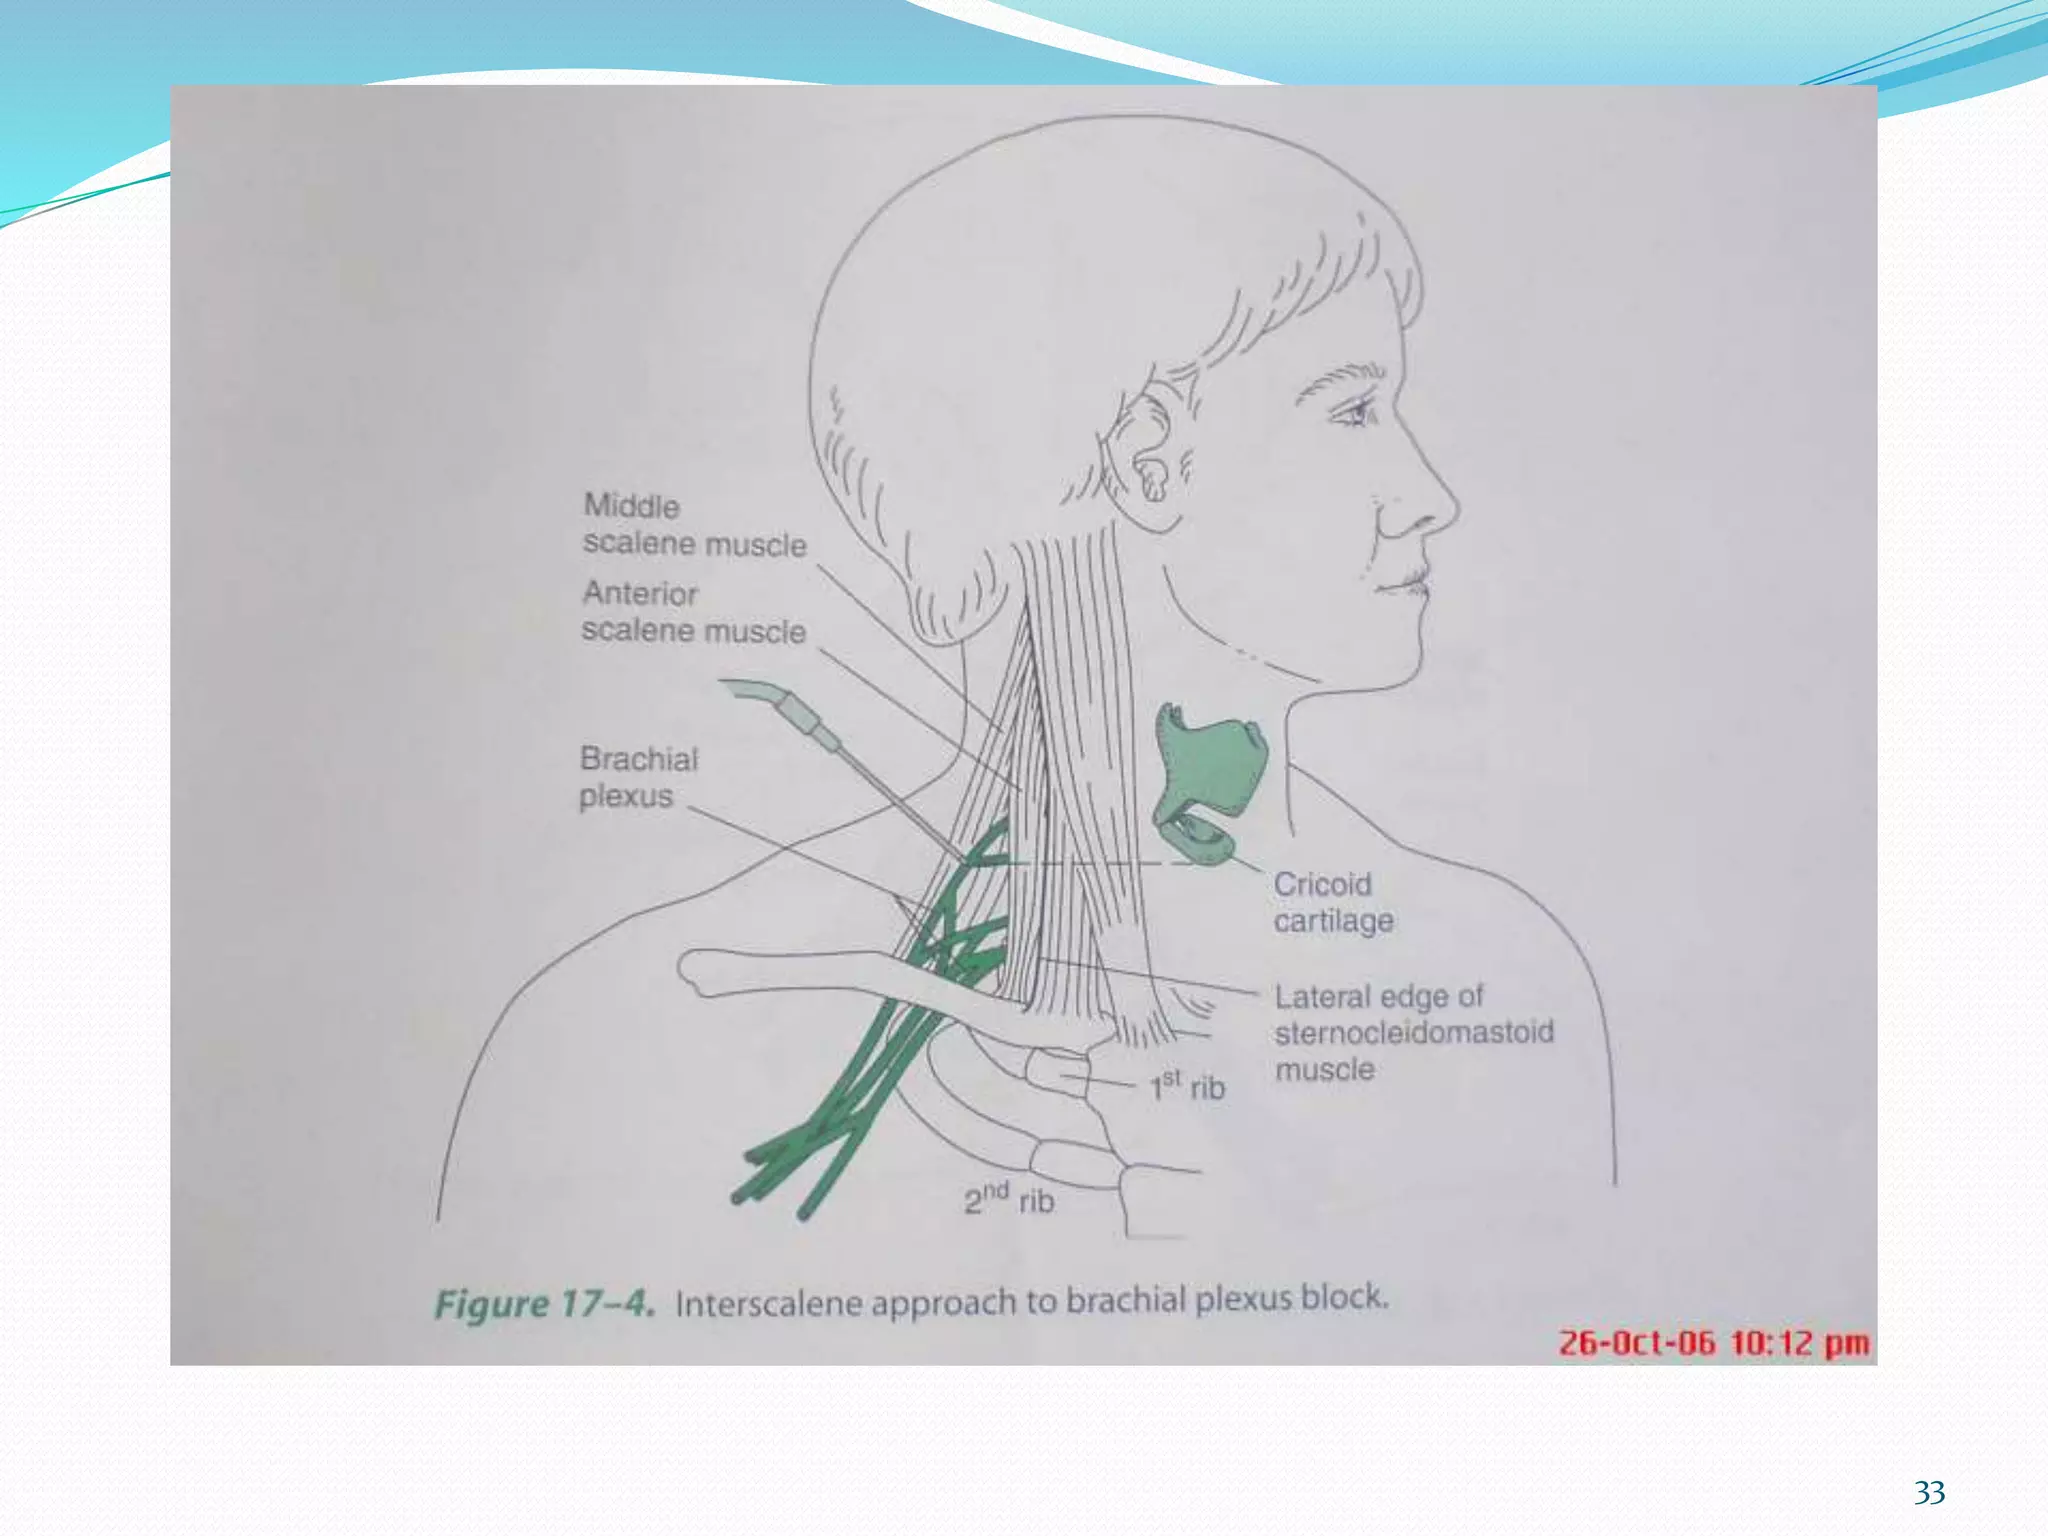

This document provides an overview of brachial plexus anatomy and techniques for brachial plexus nerve blocks. It begins with a description of the brachial plexus formation from cervical and thoracic nerve roots and its branching pattern. Four main approaches for brachial plexus nerve blocks are described: interscalene, supraclavicular, infraclavicular, and axillary. Details are provided on the anatomy and techniques for performing interscalene and supraclavicular brachial plexus blocks. Ultrasound guidance is discussed as an advancement which allows real-time visualization of needle and nerve. Complications are also summarized.